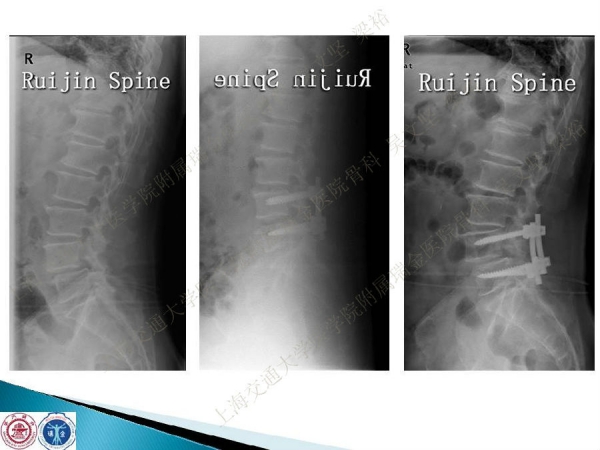

腰椎融合术后临近节段发生的退行性病变(adjacent segment disease,ASD))是一种常见的并发症。ASD的发病率相当高,而且涉及的范围很广。传统翻修手术治疗ASD有软组织剥离多、出血多、术后康复时间较长以及引起新的并发症的风险。本文结合病例介绍了运用Stand alone DLIF技术治疗ASD的方法与其优势。